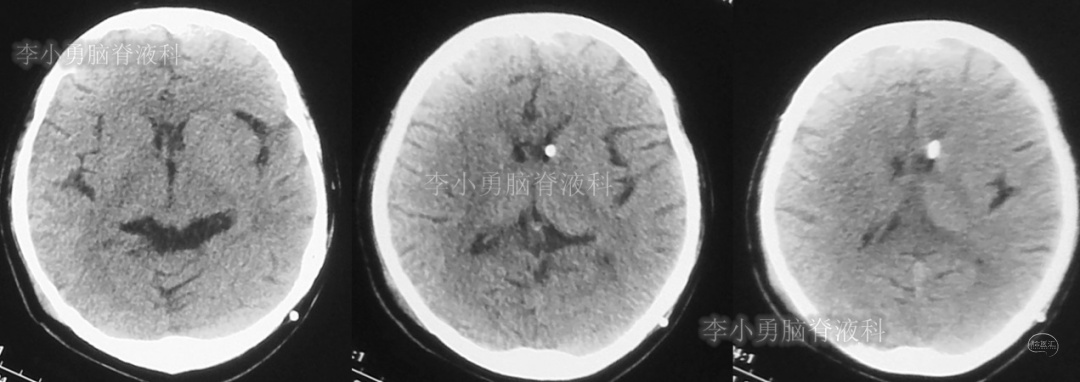

患者于2018年1月29日,突发头痛、头晕、恶心、呕吐,并高热40度。在当地医院门诊输入4天抗生素后发热缓解,但出现了双眼不能上视(眼球不能向上看)。5天后即2018年2月3日,在当地的第1家医院:浙江省海宁市某医院行头颅CT(图-1)发现脑室扩张,当地医院诊断为“梗阻性脑积水”。

图-1:2018年2月3日头颅CT